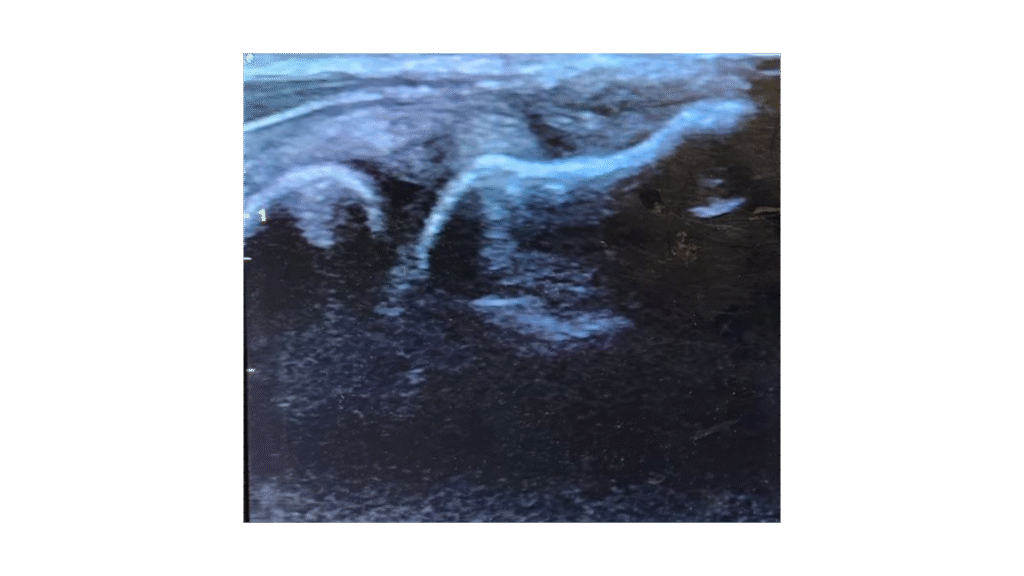

Lateral epicondylar (tennis elbow) tendon before and 12 weeks after PRP.

Notice the dark area (the tear) has filled in with new tendon.